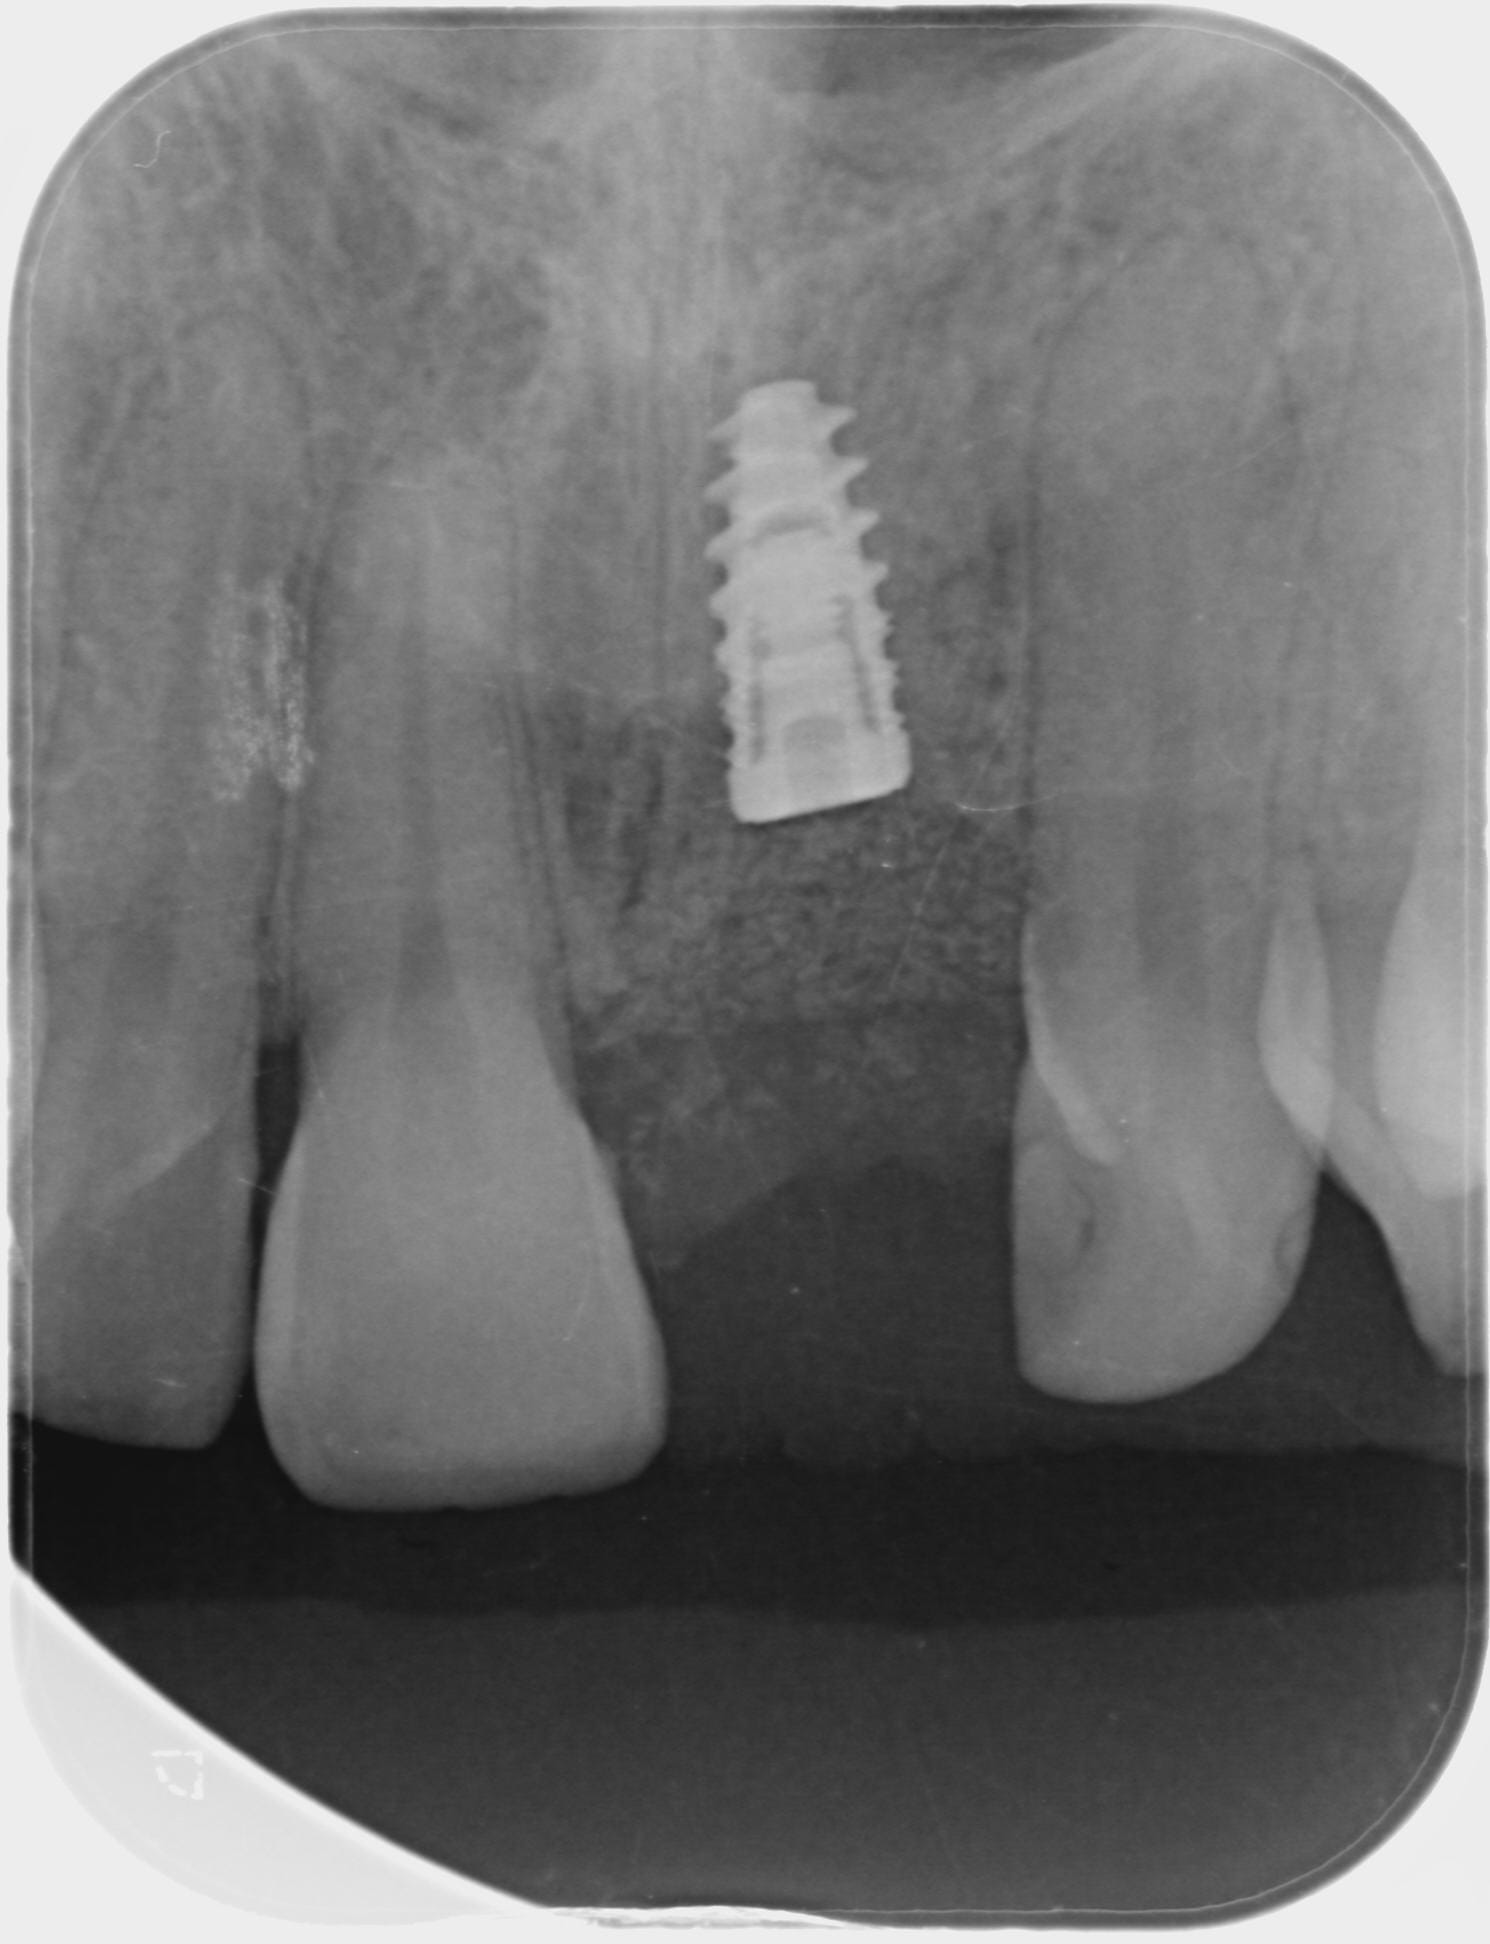

Exo de la 21 début janvier de cette année, et la semaine dernière pose d'un implant GlobalD InKone 3.5 L8.5, pose à 50-55 N.cm

Les rétros

2017 11 09 retro jour pose hwdyvj - Eugenol

2017 11 15 retro j 7 x3s3zc - Eugenol